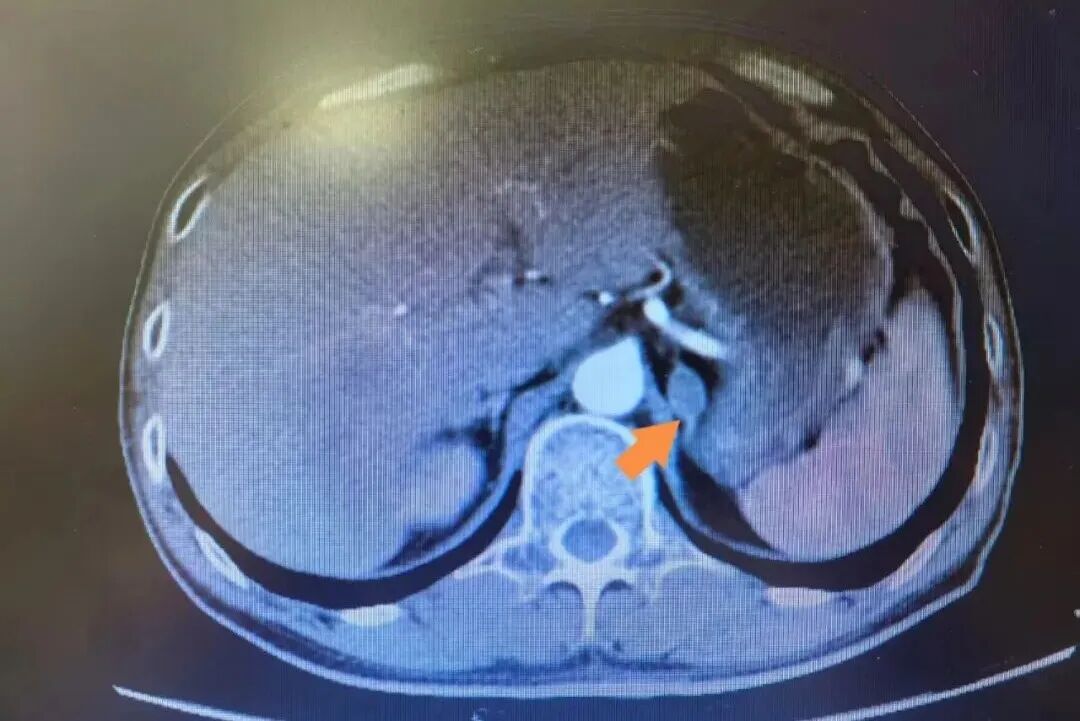

(左侧肾上腺结节灶)

入院后,接诊医生为李先生完善检查,逐项排查,最终发现其左侧肾上腺存在结节灶,结合临床症状及相关检查结果,考虑该结节为腺瘤,正是这一腺瘤导致李先生血压异常升高,属于典型的继发性高血压。